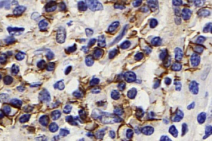

Immunohistochemistry analysis of paraffin-embedded human lung cancer using PD-L1 (GB11339) at dilution of 1:500 |